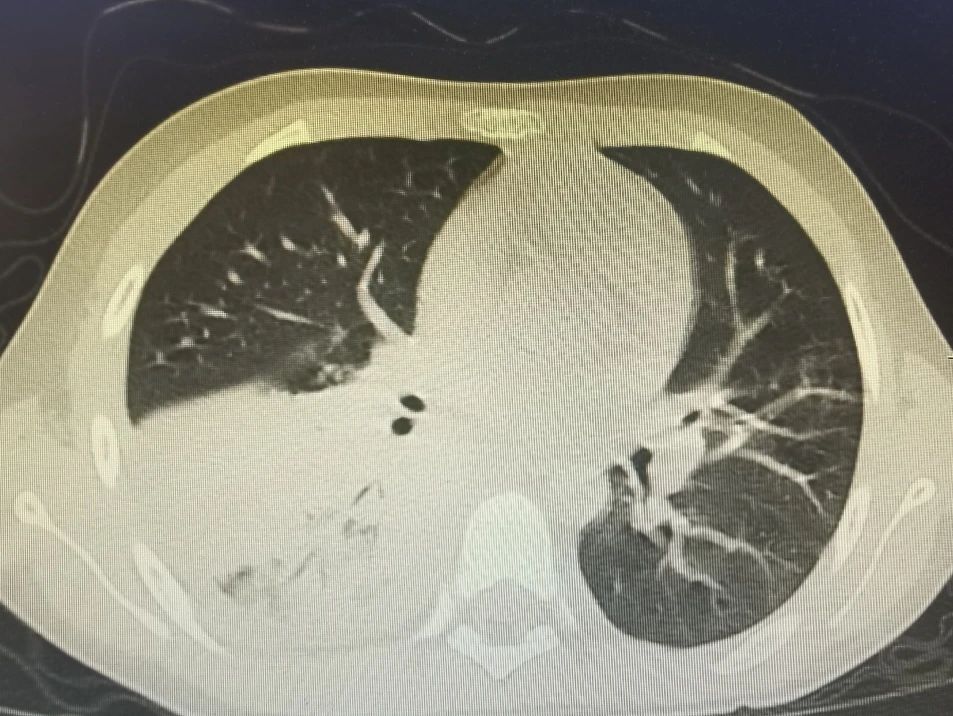

半个多月前,一名9岁的小男孩七七在父母的陪伴下,来到了锦州市妇婴医院(妇幼保健院)小儿呼吸科。因为反复高热、咳嗽10天,辗转于外院治疗6天,病情却逐渐加重,反复39-40度不退,复查的肺CT提示重症肺炎。

接诊后,当班的齐思梦医生敏锐地捕捉到重要信息:每天有将近40度的高热,持续10天;经过正规抗炎治疗6天,完全无效;合并有胸腔积液。

种种迹象表明,这是一个重症,必须积极处理。于是,在入院后的第一时间内,齐医生立即完善相关检查,并积极抗感染、雾化、营养支持等治疗,但孩子的病情仍在进一步进展。夜间,这个小男孩出现了呼吸急促,经皮血氧饱和度下降,这时候,血化验结果陆续回报,炎症指标飙升,血凝指标近10倍增高……马上吸氧,抗凝等对症处置。与刘铁英主任和王晓巍副主任沟通会诊,科室迅速召开重症讨论,定下治疗方案。齐医生耐心详细地向家属交代患儿目前需行支气管镜介入治疗,得到家属的签字同意后,于入院第2天即完成了第一次支气管镜介入治疗, 30分钟后孩子就安全返回病房,术中吸出3个较大的“树枝样”塑型痰栓及数个小痰栓。术后当晚,孩子精神状态明显好转,食欲增加,家属高兴的对医生们说:“你们太厉害了,这一天就精神了”。

节假日期间,七七出现了间歇性胸痛,疼出了眼泪,又出现了一次低热,家属的心再一次提到了嗓子眼儿。刘铁英主任连忙赶到医院看望他,担心重症肺炎可能出现恢复期的肺栓塞,又紧急联系放射线,放射线曹主任马上安排会诊给他急查了肺增强CT。结果出来后没有发生栓塞,医护人员和家属都松了一口气,考虑跟胸水吸收后引起的胸膜牵扯痛有关系,对症处置后2-3天胸痛消失,发热也很快消失。